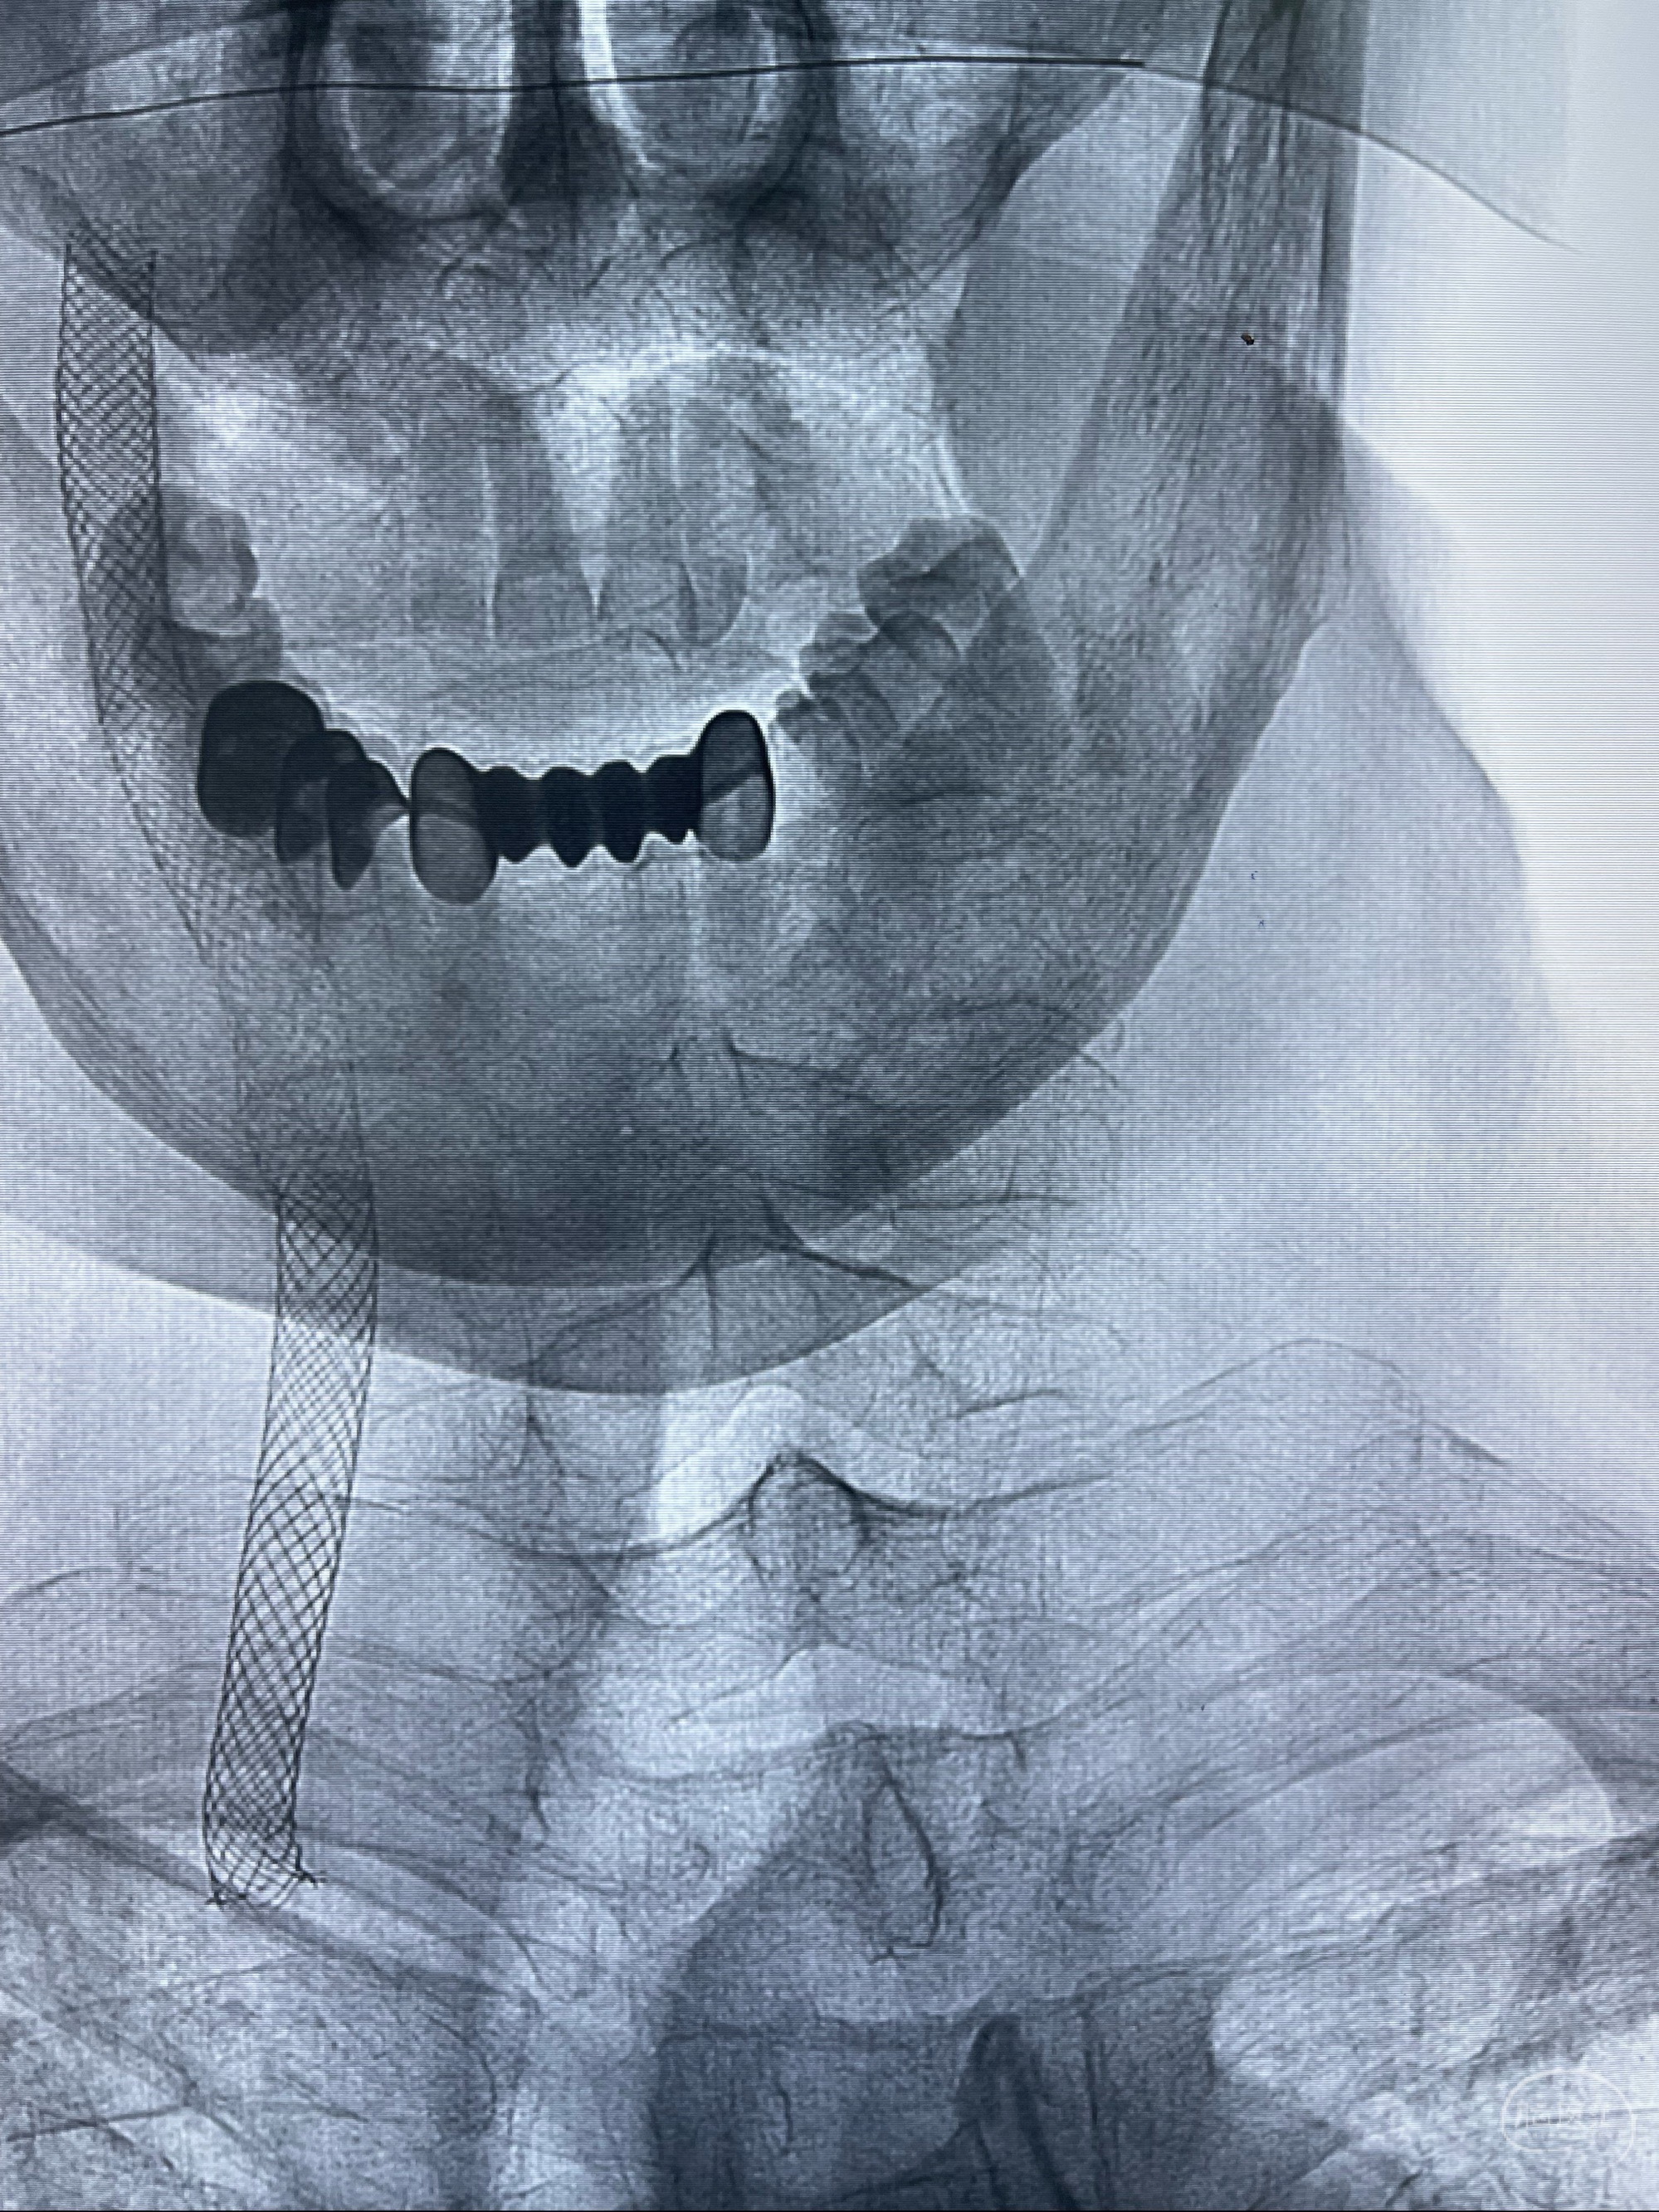

2023-07-10DSA:右侧颈内动脉岩骨段夹层伴中偏重度狭窄改变,左侧颈总动脉闭塞、右侧颈外动脉由右侧肋颈干甲颈干吻合代偿

箭头所示为颈内动脉岩骨段重度狭窄,结合MRI,考虑为肿瘤侵犯右侧颈内动脉

箭头以近至支架段管腔不规则狭窄

双抗准备后于2023-07-13在全麻下行右侧颈内动脉功能保护

088NeuroMAX100cm长鞘在125cmMPA及黑泥鳅导丝引导下超选择性插入右侧颈内动脉支架内

经导引导管造影显示支架远端颈内动脉不规则狭窄伴局部充盈缺损,同时行全身肝素化5ml